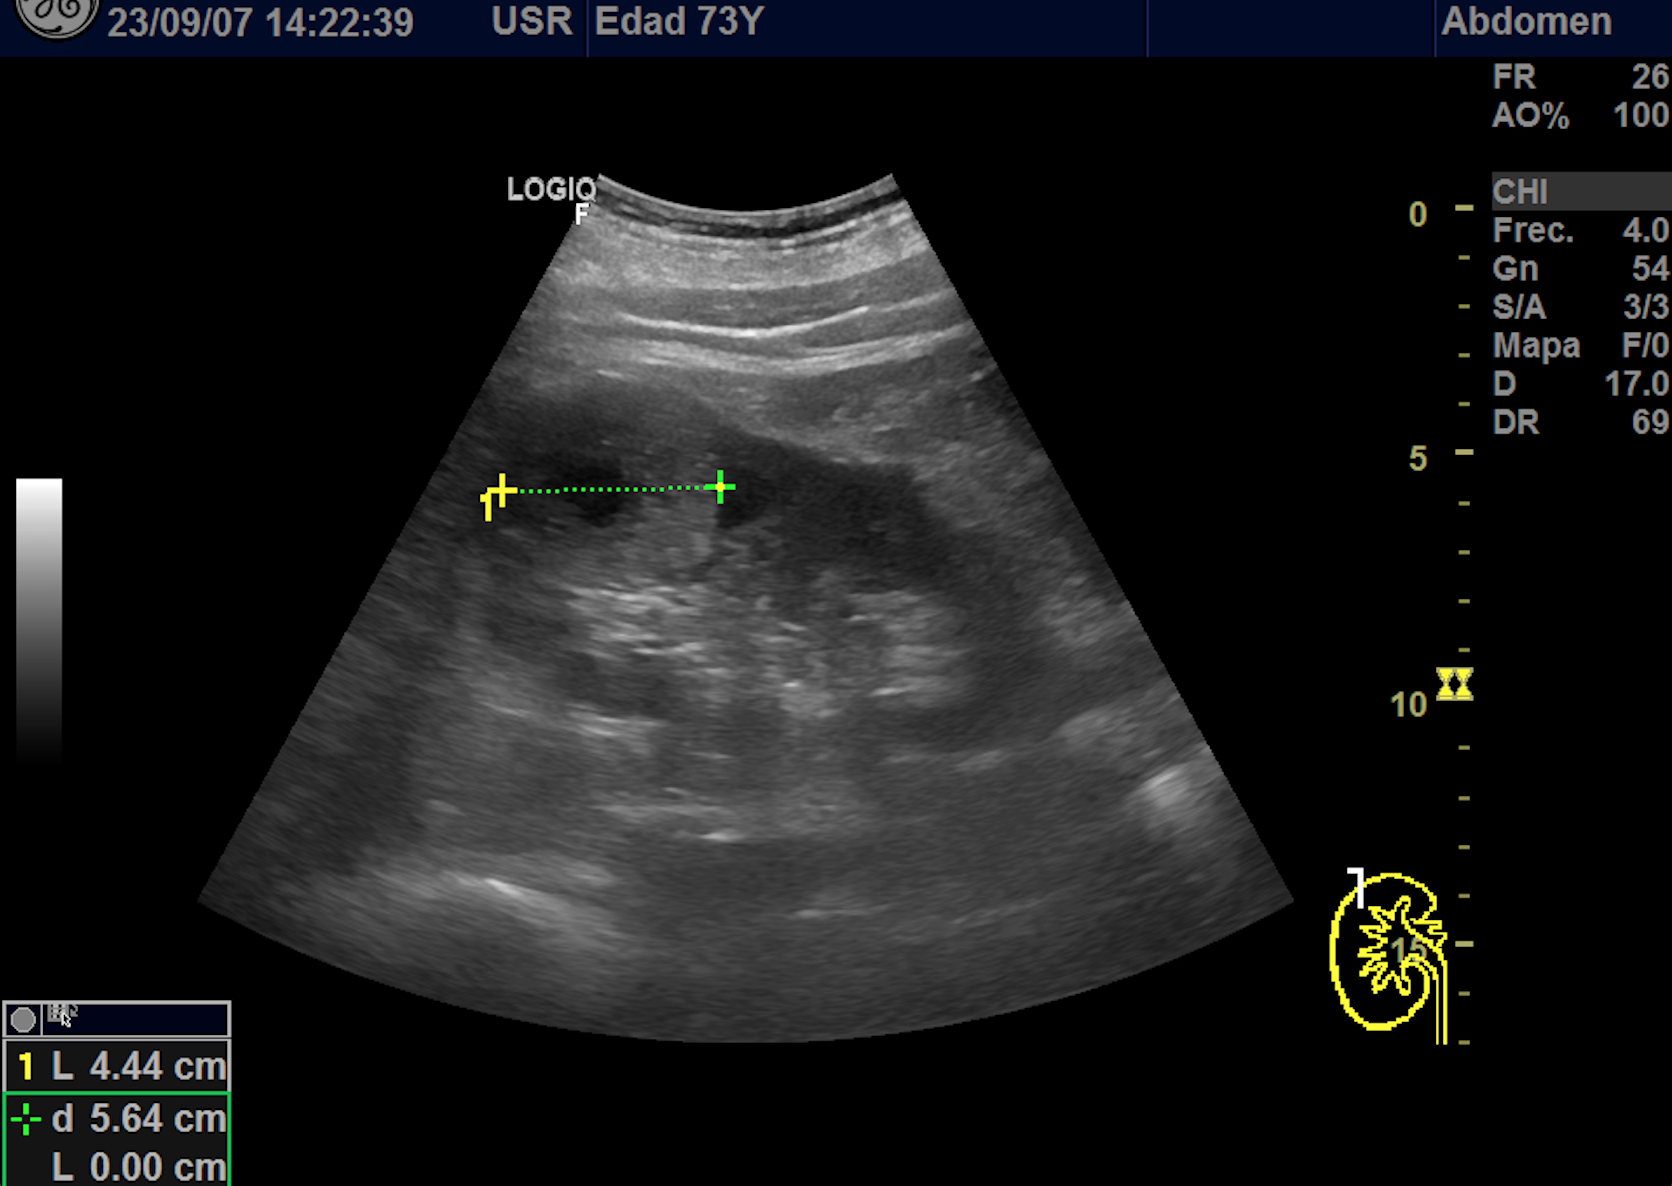

Hallazgos ecográficos

En polo superior de riñón derecho se observa una imagen redondeada, bien delimitada, isoecoica con un área central hipoecoica con vascularización periférica y central de 4,1 x 4,18 x 4,94 cm.